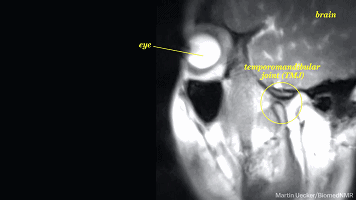

这时候,由于肾上腺素分泌的原因,你可能会出现短暂的瞳孔放大,眼睛的

焦距增强。

当然了,你可能不会有太大明显的视觉上的变化,但有研究证明:

人在情绪激动的时候,瞳孔可以放大到原来的5-10倍左右,进入一种精神亢奋的状态。

这时候的人眼往往看起来更大更有神,甚至,你会觉得对方眼睛在发光。

(左:眼镜;右圆圈处:颞下颌关节)